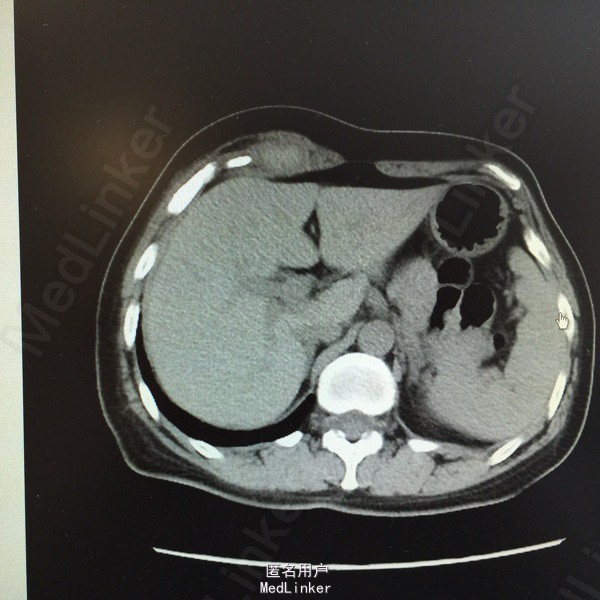

主诉:腹痛、发现腹部肿物15天。 现病史:患者于15天前因运动后突发腹痛,为持续性胀痛,伴停止排气,无恶心、呕吐,后觉疼痛缓解,并发现腹部肿物,压痛明显。当时于外院行超声:右上腹患者所指处肌层见无回声,约8*6cm大小,形态规则,边界清。现患者无诉疼痛,自觉肿块变小,为进一步诊治,收入我科。 既往史、家族史均无特殊。 查体:全腹软,右上腹近季肋部可触及一5*2cm包块,质软,活动差,压痛明显,周围皮肤无红肿、无溃烂。余无特殊。 辅助检查: 超声:患者右上腹腹壁层内肌层后方见无回声,大小约5.4*2.3cm,形态规则,边界尚清,内见少许分隔。考虑右上腹腹壁内囊性包块。 CT:右上腹季肋部腹直肌鞘内梭形软组织密度影,病变中央密度高,约65HU,边缘密度稍低,约33HU。印象:右上腹腹直肌鞘内梭形高密度影,血肿不除外。 大家考虑?